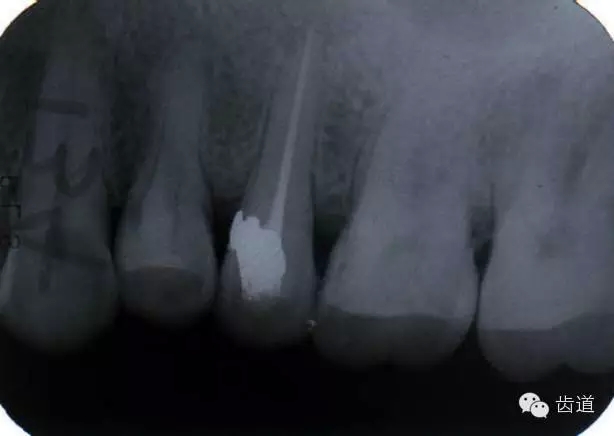

左上5牙頸部側(cè)穿

左上4鑄造樁側(cè)穿

左上7近中頰根器械折斷

右上6腭根器械折斷